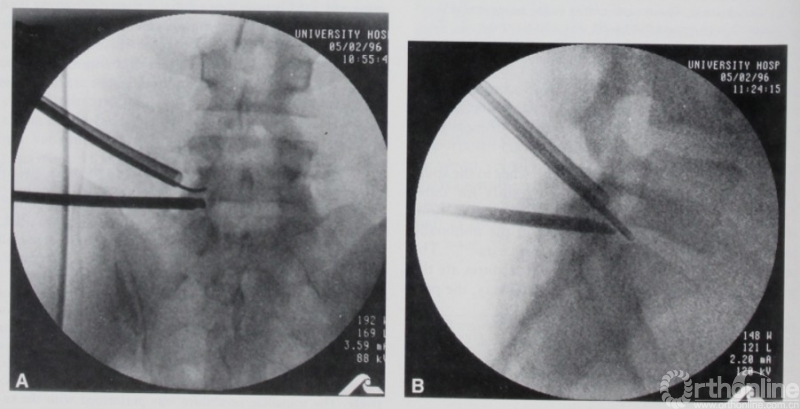

Osman在1994发表[16]描述了胸腰椎后外侧关节镜间盘切除术(Posterolateral arthroscopic discectomies of the thoracic and lumbar spine),确定了入路以及入路相关解剖。在1997年发表的经髂骨入路内镜处理腰5/骶1节段的解剖研究中作者报道了他所使用的单侧双通道脊柱内镜技术[17]。

图4. 1997年Osman使用的单侧双通道脊柱内镜技术。引自Osman SG, Marsolais EB. Endoscopic transiliac approach to L5-S1 disc and foramen. A cadaver study. Spine (Phila Pa 1976) 1997;22(11):1259-1263.